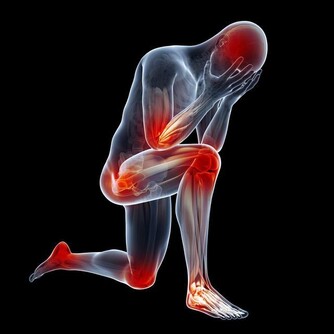

通常發生在人進行劇烈運動目大量出時,人身體中的鹽分和水分隨汗液一同流失。肌肉中的含鹽量低可能是造成熱痙攣的原因。此外,停攣也可能是熱衰竭的一種表現。

表現為肌肉或抽描,發生在腰部手臂或部。常呈對稱性,時而發作。患者意識醒,體溫一般正常。